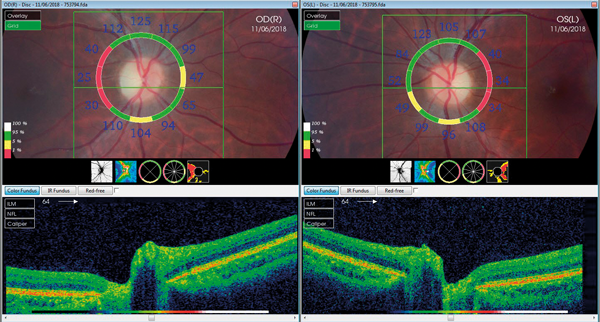

What not to miss in neuro-ophthalmology Part 2

As mentioned previously there are several conditions in neuro-ophthalmology that should not be missed by the general ophthalmologist as well as ophthalmology trainees. We discussed in the first part some of these conditions including third cranial nerve palsies, giant cell...

What not to miss in neuro-ophthalmology Part 1

Neuro-ophthalmology is a complex and difficult subspecialty in ophthalmology. It has several connections to neurology, neuro-surgery, rheumatology as well as many other medical specialties. Working in an multidisciplinary team (MDT) environment is key to success in this subspecialty as mistakes...